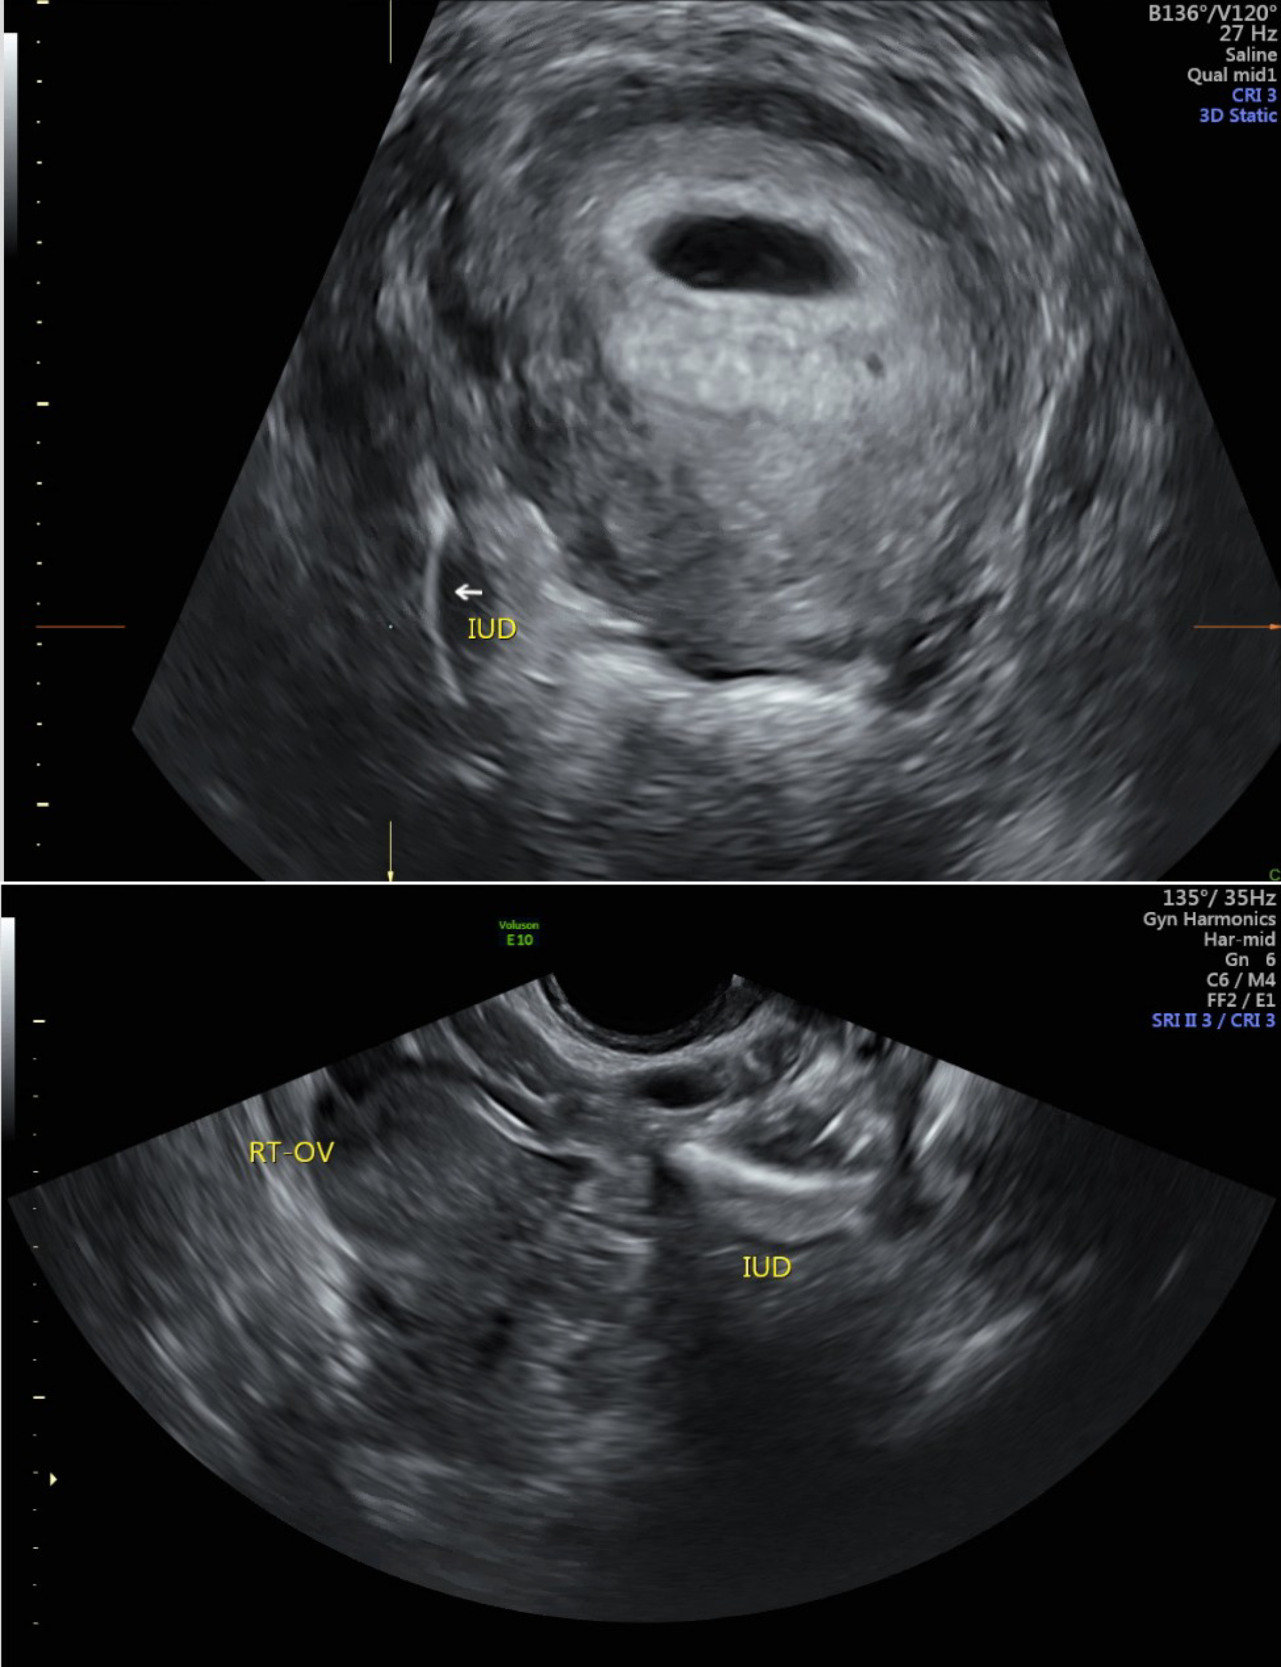

The patient was referred to our family planning clinic seeking induced abortion and IUD localization and removal. Transvaginal ultrasound confirmed intrauterine pregnancy at 6 weeks and 3 days and identified the IUD in the right adnexa (Figure 1). After counseling, the patient had an uncomplicated medical abortion with plan for laparoscopic IUD removal upon abortion completion.

_intrauterine_device_seen_in_right_adnexa_on_3-dimensional_ultrasound._(b)_intrauterine.png)